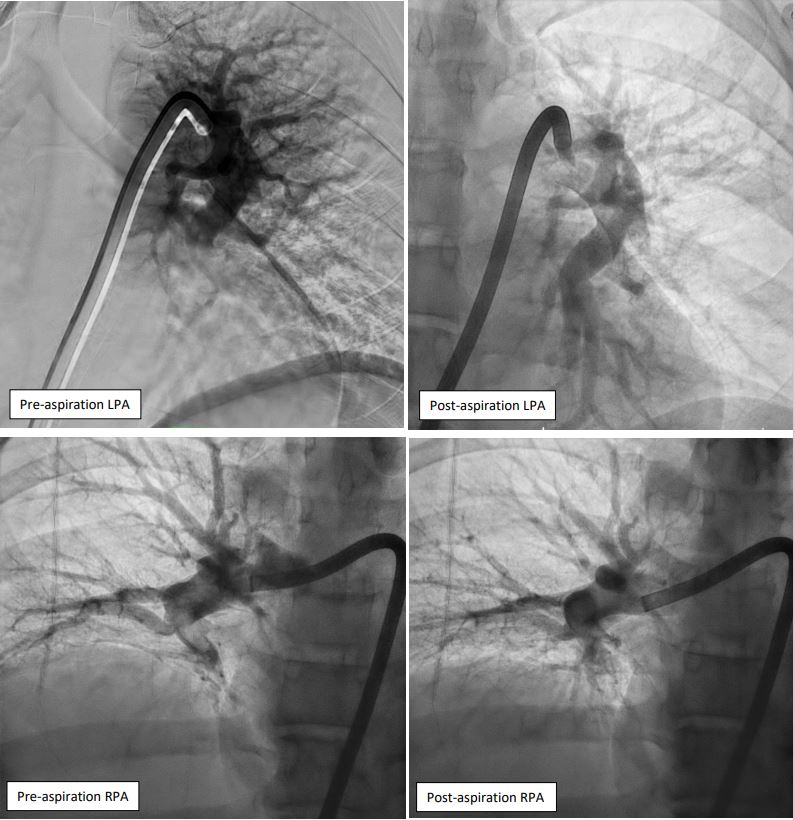

Right femoral vein access was obtained under ultrasound and fluoroscopy guidance. A 6Fr multipurpose (MP) catheter was used to deliver a J-tip guidewire into the main pulmonary artery, which was then exchanged for a pigtail catheter. Digital subtraction angiography revealed filling defects in the truncus anterior and bilateral interlobar arteries. The 6Fr femoral sheath was upsized to a 16Fr sheath. The Penumbra ENGINE and Lightning Flash 2.0 system, with a 16Fr aspiration catheter, was primed. Using the MP catheter, the J-tip guidewire was delivered into the left pulmonary artery and exchanged for the 16Fr aspiration catheter. Multiple aspiration runs were performed using the computer-assisted vacuum thrombectomy system. The same steps were repeated for the right pulmonary artery. The procedure lasted 2 hours, with 1.2L of blood loss and approximately 6-8 cubic centimeters of fresh clots aspirated. The patient received 2 units of packed red blood cells during the procedure. Femoral access was closed with a figure-of-8 suture.